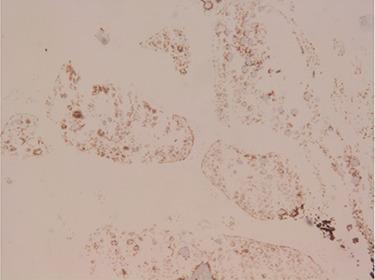

Sex cord tumour with annular tubules (SCTAT) is uncommon and distinctive type of sex cord-stromal tumours of the ovary which develops from sex cord cells. Most of SCTATs are strongly associated with Peutz-Jeghers syndrome (PJS) and have low malignancy potential; however, 20% of non-PJS-associated SCTATs have been reported to have high malignancy potential. Herein, we present a 13-year-old female who presented with severe abdominal pain localized in the right lower side, associated with nausea. Based on histopathological and immunohistochemical findings, the diagnosis was confirmed to be SCTAT. SCTAT of the ovary is extremely rare in the paediatric population as compared to the general population. Its occurrence among paediatrics as it was the case in the patient described in this paper may pose diagnostic challenges due to lack of clinical suspicion and therefore resulting in delay of diagnosis.

伴有环状小管的性索肿瘤(SCTAT)是一种罕见且独特的卵巢性索间质肿瘤,由性索细胞发展而来。大多数SCTAT与黑斑息肉综合征(PJS)密切相关,恶性潜能较低;然而,据报道,20%的非PJS相关SCTAT具有较高的恶性潜能。在此,我们报告一名13岁女性,她出现严重腹痛,局限于右下腹,并伴有恶心。根据组织病理学和免疫组化结果,确诊为SCTAT。与普通人群相比,卵巢SCTAT在儿科人群中极为罕见。由于缺乏临床怀疑,其在儿科中的发生情况(如本文所述患者)可能会带来诊断挑战,从而导致诊断延迟。